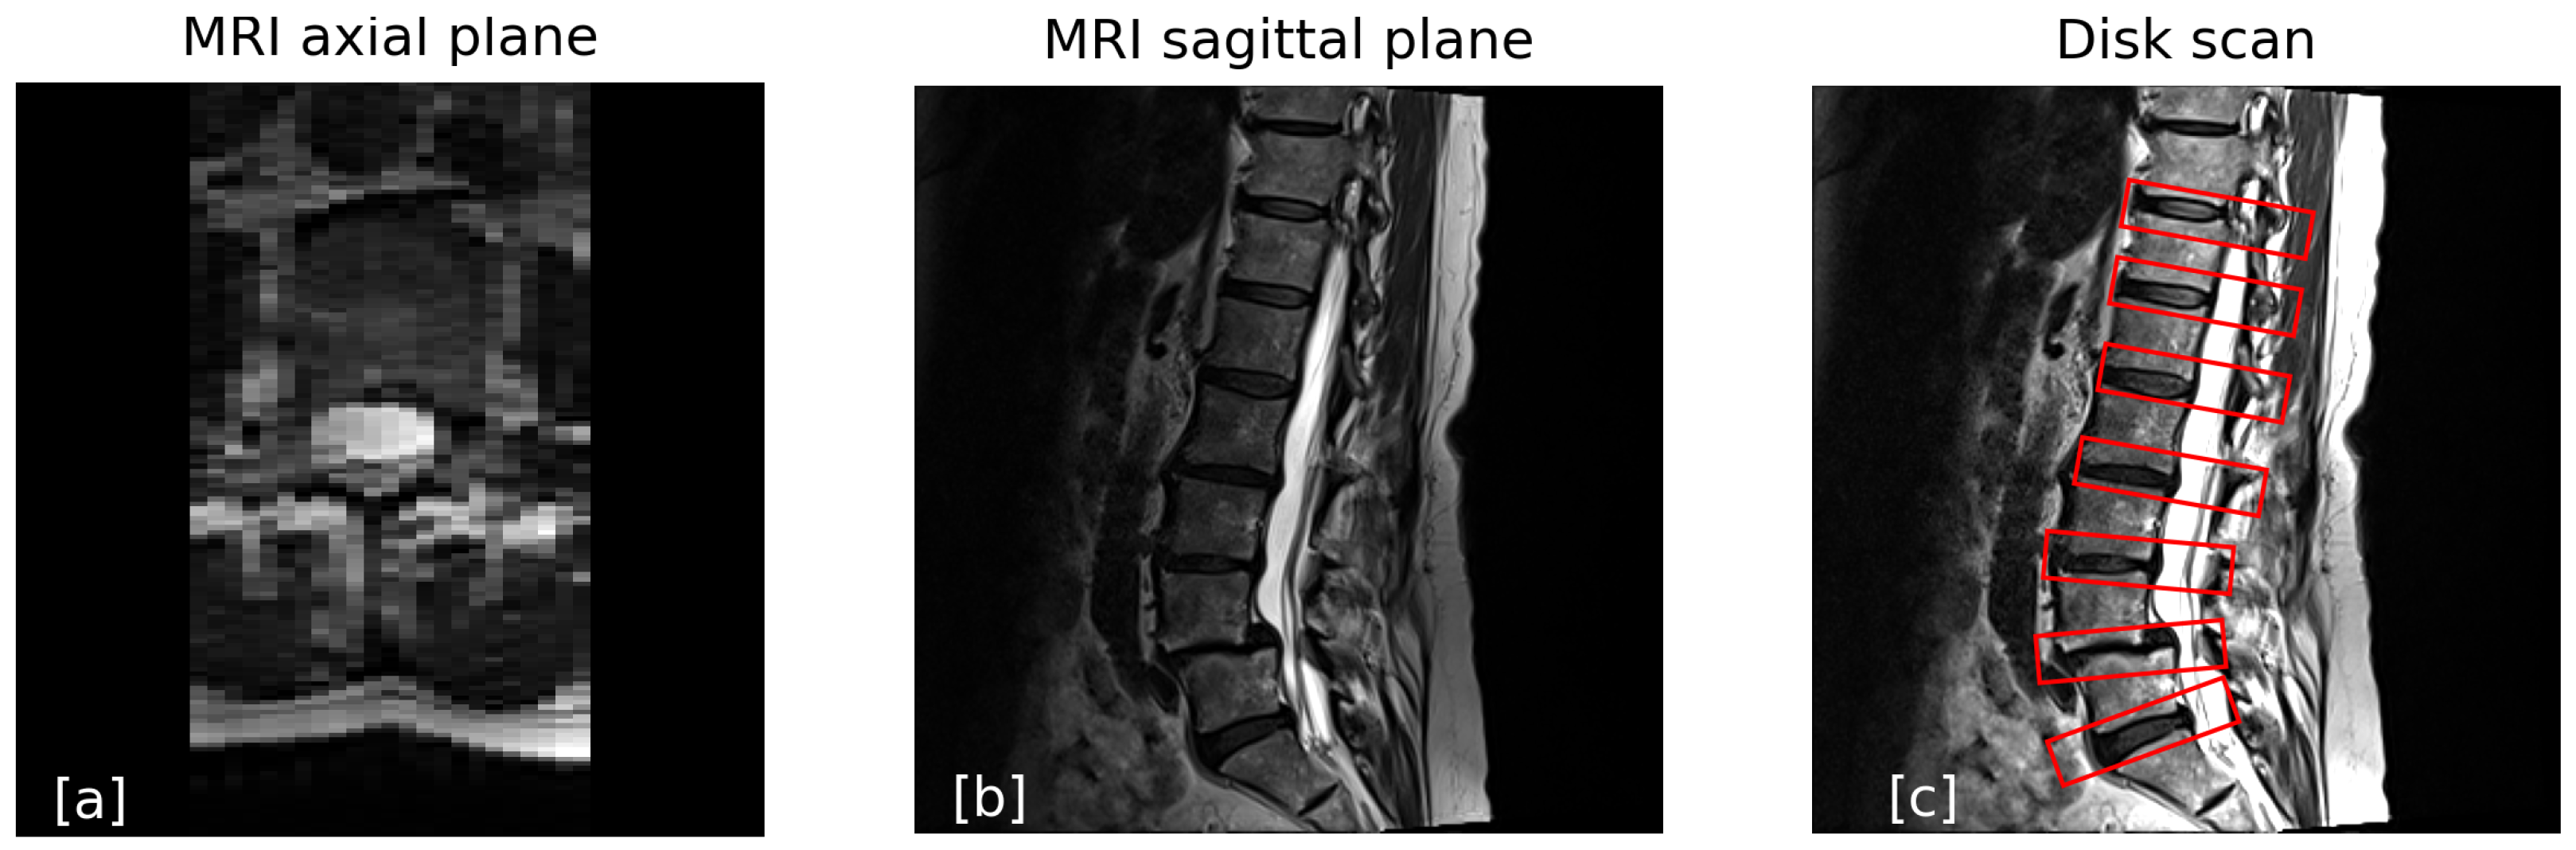

- A sagittal scan using both T1- and T2-weighted protocols. These scans have a low resolution in the left–right (LR) direction, with slice thicknesses ranging from 3 to 5 mm, depending on the site-specific protocol. In these cases the axial slice is not usable as its resolution is low, and only the sagittal slice is used, as seen in Figure 1.

- Scanning only the intervertebral disks while skipping the vertebrae, as shown in Figure 1c.